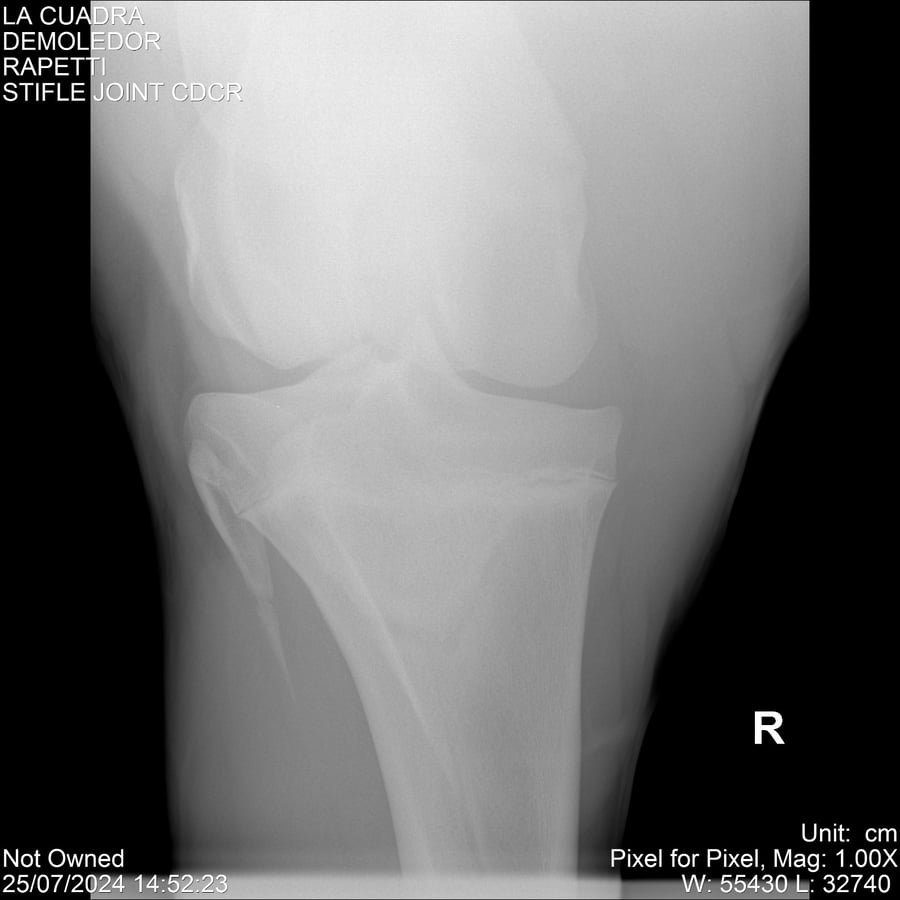

LOTE 14, DEMOLEDOR 🔥 🔥 🔥 Lote Anterior Volver al remate Lote Siguiente Ficha Contacto Montevideo - Ficha del Lote Identificador: #284454 Categoría: Yeguarizos Montevideo - 89 Visualizaciones ClicData Contacto Empresa: Abelenda N. R., Walter Hugo Nombre*: Teléfono* : E-mail* : Mensaje Enviar Registrese gratis Este contenido Exclusivo está disponible sólo para usuarios registrados Ingresar